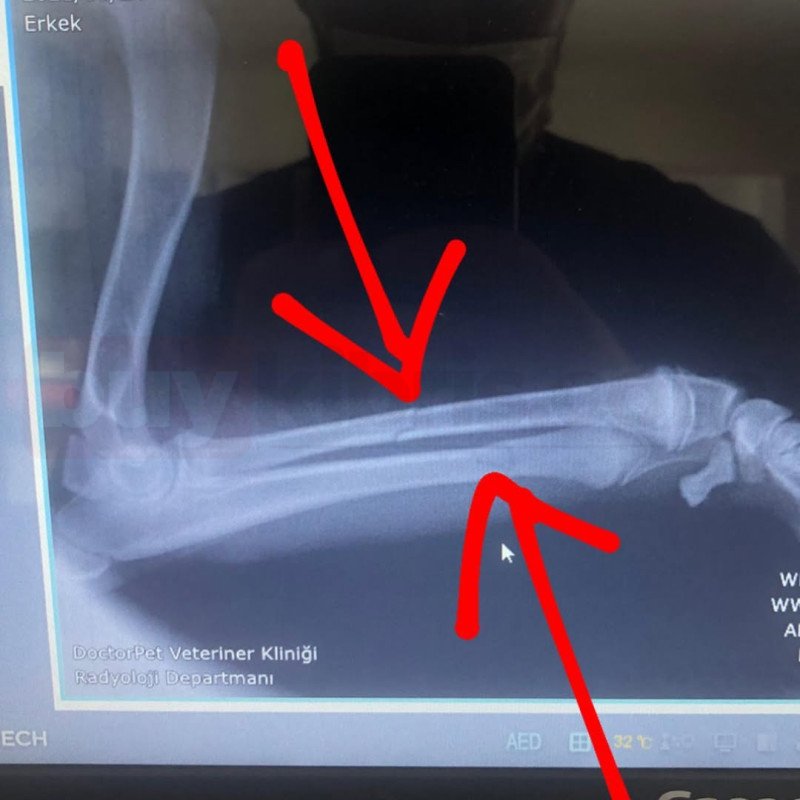

Yine bir trafik kazası sonucu ayağı kırılan hastamızın klinik ve radyolojik mueyenesinin ardından tedavisini yapıp evine gönderdik. Gecmiş olsun evlat 🐾😊